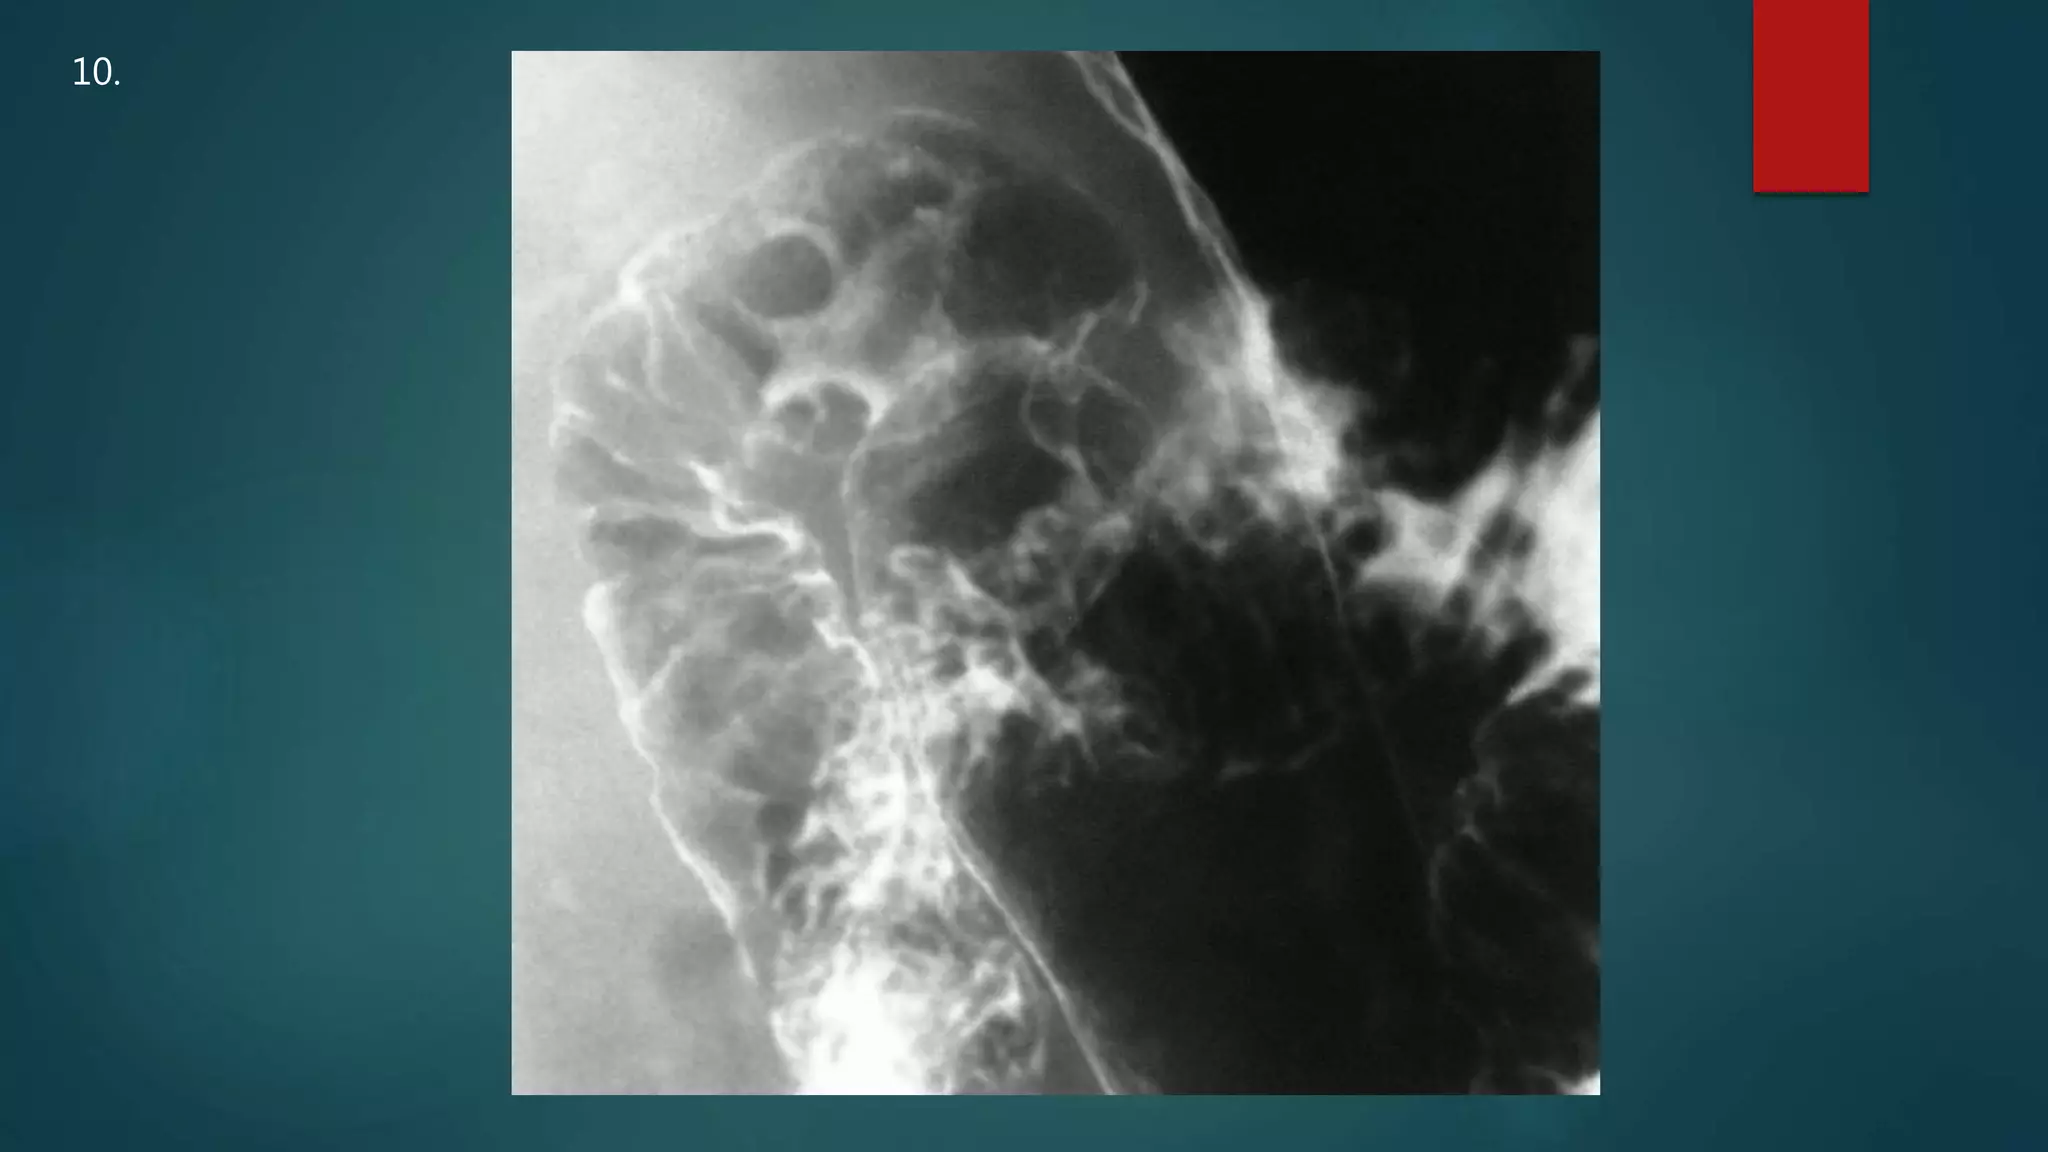

This document appears to be a medical report discussing several patients. It mentions a 35-year-old who was in a severe motor vehicle accident and an 81-year-old with a history of a non-vegetarian diet who had a perforated bowel from a chicken bone. The document provides few other details across its 25 numbered entries and was authored by Dr. Anish Choudhary for junior year 3 on May 30, 2016.